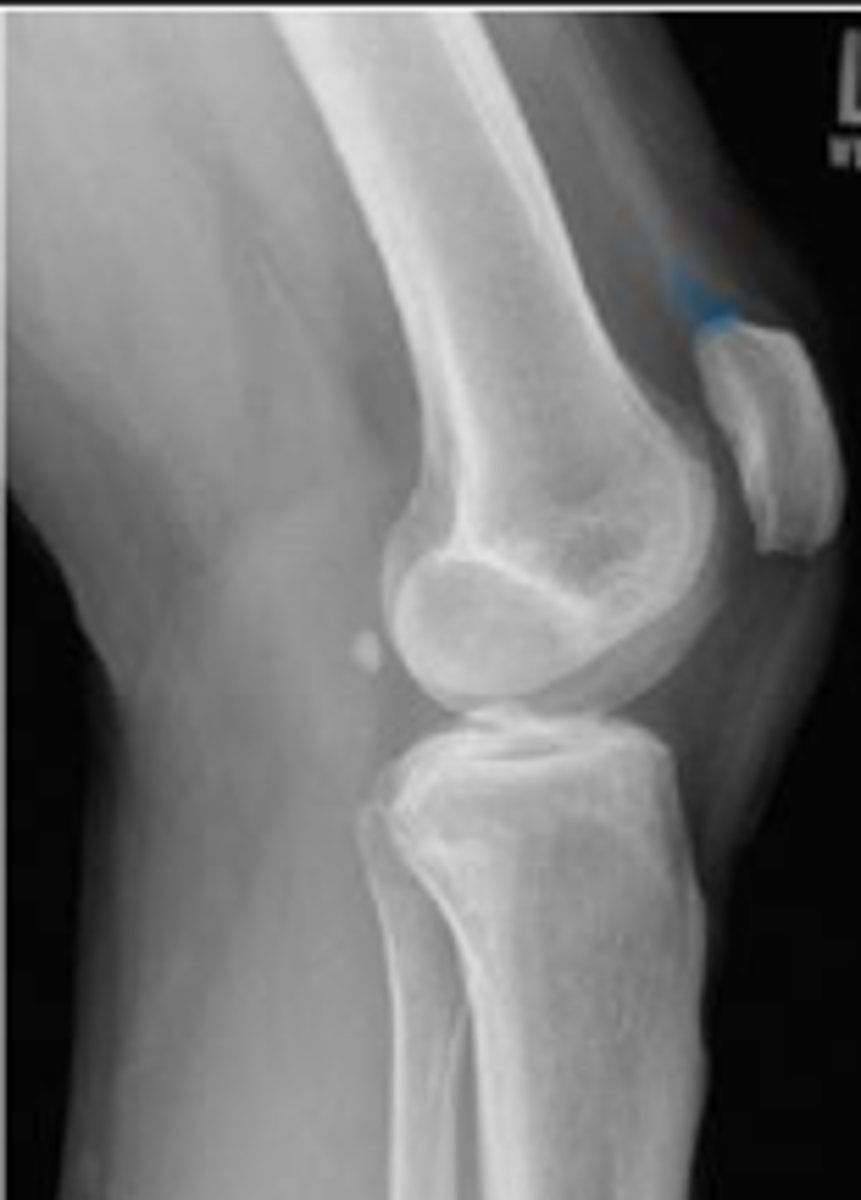

Lateral collateral ligament

What inserts at the location of the blue arrows?

Lateral collateral ligament avulsion fracture of

the right knee

What is the most significant radiographic finding?